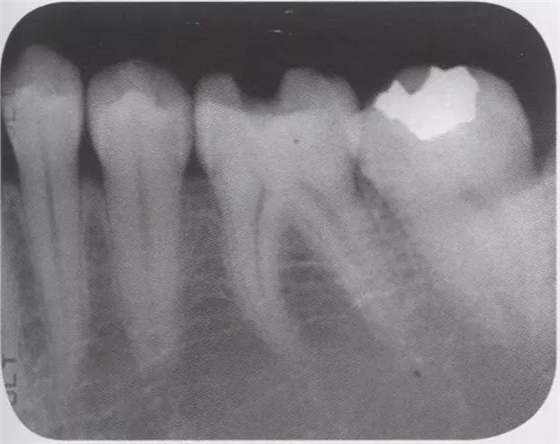

1、嵌體和高嵌體 在磨牙區(qū)域,由于牙齒近中面以及遠(yuǎn)中面的傾斜程度不同,常會遇到分離困難的病例。例如,智齒的近中根傾斜,引起鄰牙根間隙過窄的情況。相鄰牙齒的近中傾斜,牙冠進(jìn)入被處理牙倒凹處的情況(圖2、3)。以上情況,鄰接面由于齲齒形成窩洞,即便是運(yùn)氣好在齦下做了分離,也會因為出血造成取模困難、頰舌的成形變大。所以采取以下處理措施。 1、術(shù)前拍攝牙片,根據(jù)牙根的傾斜判斷有沒有引起鄰牙根間隙過窄的情況。若沒有傾斜,就是簡單病例。 2、若智齒沒有對合牙,也考慮拔除智齒。 3、鄰接面用樹脂填充之后,用間接法進(jìn)行烤瓷嵌體或烤瓷高嵌體修復(fù)。 1、貼面治療 對于變色牙齒進(jìn)行貼面治療的情況下,牙頸部觀察無變色的情況下,可直接在齦上做成形。普通成形深度能夠保存牙釉質(zhì),因而判斷為簡單病例。(圖4) 如果牙頸出現(xiàn)變色,就需要進(jìn)行齦下成形,難度增加。如果也存在前突問題,為改善變色貼面不能做厚,因而難度會更高。如果希望糾正前突、改善變色,則需要增加切削量,甚至可能進(jìn)行拔髓。另外,由于粘接對象主要是牙本質(zhì),因而需要格外注意。

圖1 智齒向遠(yuǎn)中傾斜病例

圖2智齒嵌入被處理牙鄰接面的倒凹,即便分離成功,成形范圍也會變大。

圖3鄰接面成形困難的病例。如圖所示右下7近中傾斜,窩洞成形的遠(yuǎn)中側(cè)有缺損(上左),所以遠(yuǎn)中部需要在齦下做很深的成形(上右),因而選擇在遠(yuǎn)中先進(jìn)行樹脂填充后(上右)。進(jìn)行MO窩洞修整后做全瓷嵌體試戴(下)。